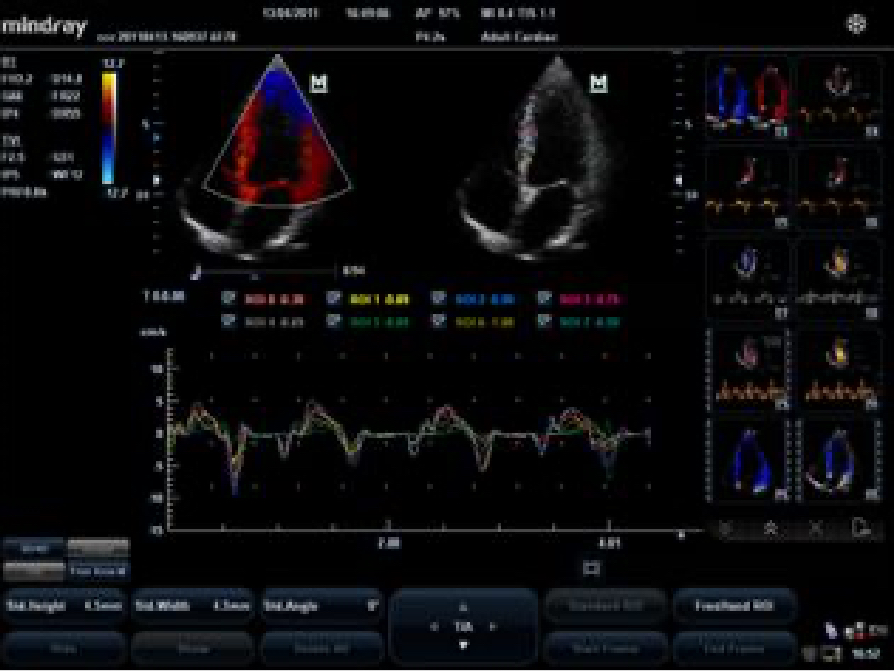

Gain precise anatomical observation by freely placing sample lines at any angle. Attain better images through simultaneous display of up to 3 sample lines.

Accurately evaluate myocardial motion at different phases, and simultaneously determine myocardial synchronization. High frame-rate providing you with accurate results.